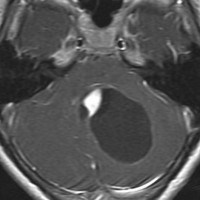

小児期の毛様細胞性星細胞腫

10才小児の小脳結節性毛様細胞性星細胞腫です。典型的な良性腫瘍として知られる毛様細胞性星細胞腫です。